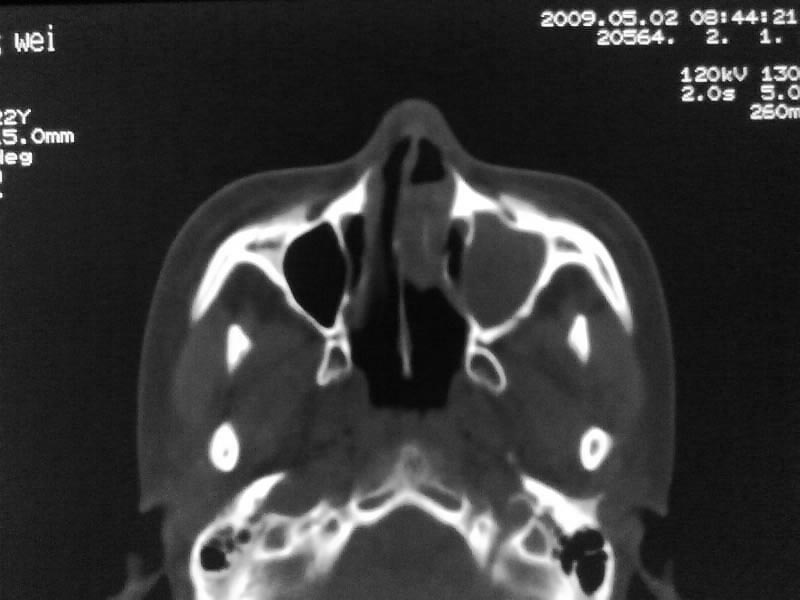

以下是引用zjzjr在2009-5-3 9:59:00的发言:[br]左侧鼻腔息肉、左侧筛窦、上颌窦炎症。双侧下鼻甲粘膜肥厚。

以下是引用随光逐影在2009-5-3 13:02:00的发言:[br]1)左侧鼻腔新生物(息肉可能)。2)左侧上颌窦及左侧筛窦炎症。3)双侧下鼻甲黏膜肥厚。